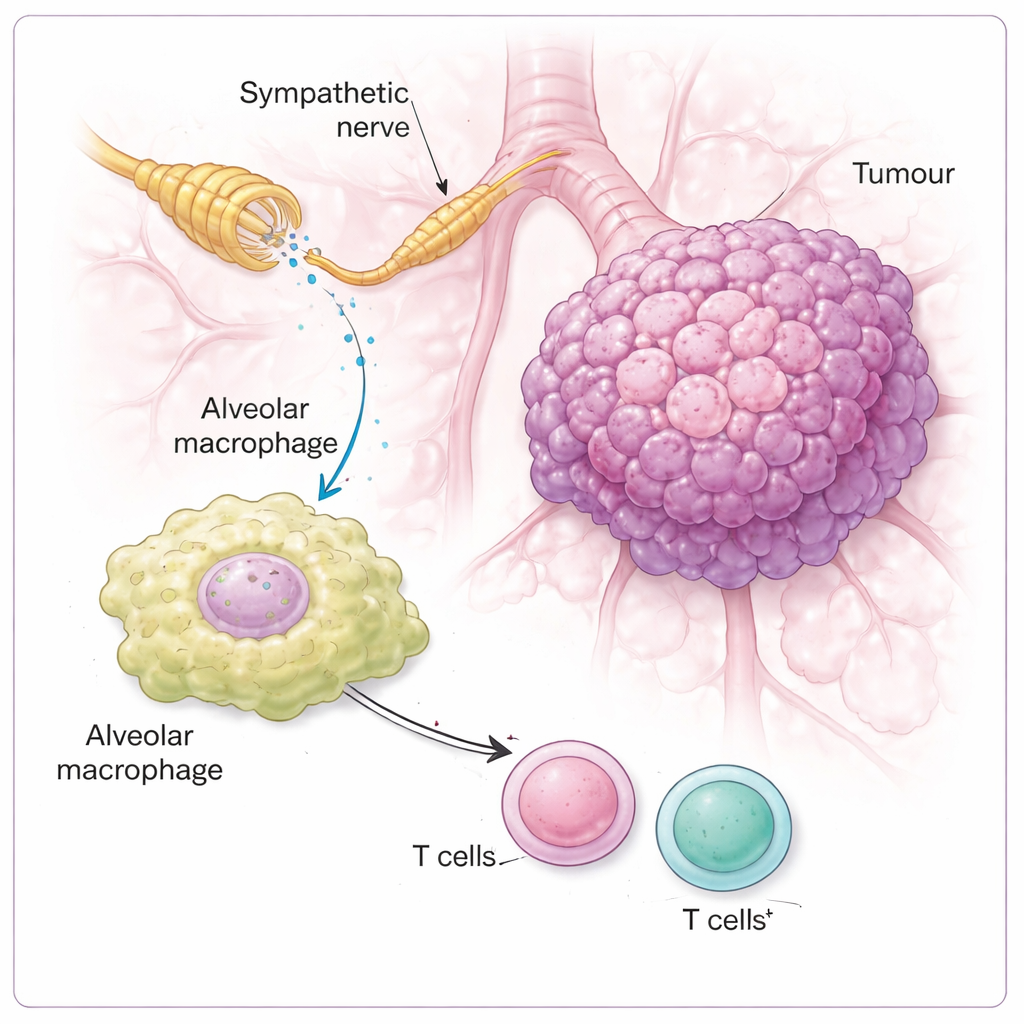

Spegnere le cellule immunitarie tramite intermediari locali

Lo studio ha quindi chiesto quali cellule nel quartiere tumorale «ascoltano» effettivamente i segnali simpatici. Sorprendentemente, la noradrenalina ha avuto scarso effetto diretto sulla crescita delle cellule tumorali in coltura. I principali recettori erano invece le cellule immunitarie, in particolare i macrofagi alveolari—cellule sentinella che risiedono negli alveoli polmonari. Questi macrofagi esprimevano alti livelli di un recettore chiamato recettore β2-adrenergico, che percepisce la noradrenalina. Quando questo recettore mancava, o quando la segnalazione della noradrenalina era bloccata, i tumori crescevano meno e l’attacco immunitario da parte delle cellule T diventava più forte. Nei topi con circuito nervoso intatto, la noradrenalina spingeva i macrofagi verso uno stato più soppressivo, segnato da livelli più elevati di un enzima chiamato ARG1, noto per attenuare le cellule T. Una volta riprogrammati in questo modo, i vicini linfociti T CD4 e CD8—normalmente gli efficaci uccisori del cancro—erano meno in grado di dare una risposta robusta.

Perché questo è importante per la terapia del cancro